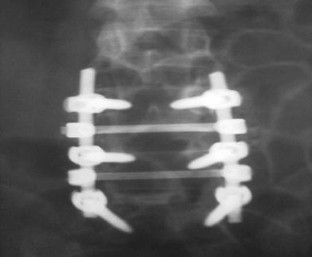

We report a case of L4–L5 traumatic anterolisthesis. The patient was treated surgically 4 months after the injury. His radiological and operative findings showed L4 inferior facet tip fracture, L4–L5 anterior displacement and left L4–L5 foraminal disc protrusion. Decompression, reduction with L3, L4, L5 pedicular screw fixation, L4–L5 disc excision and interbody cage insertion with autologous bone grafts were done. Flexion type injury was thought to be the probable mechanism.

Fig. 1